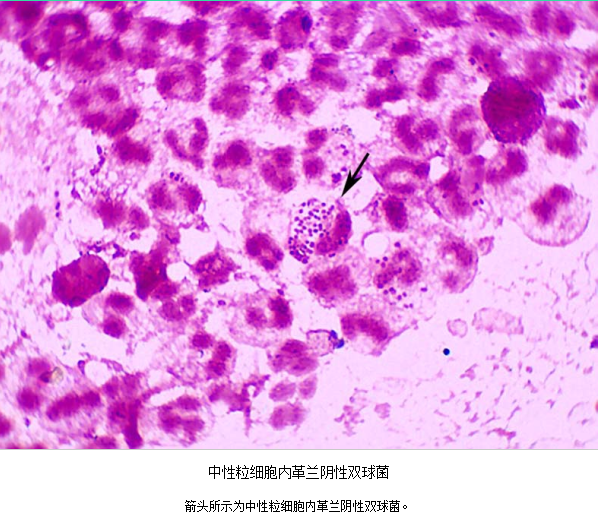

(1)子宫颈管脓性分泌物涂片作革兰染色,中性粒细胞>30/高倍视野。

急性子宫颈炎患者,子宫颈管脓性分泌物涂片作革兰氏染色,中性粒细胞>30/高倍视野,

箭头处为中性粒细胞内可见革兰氏阴性双球菌

3.病原体检测 应作衣原体及淋病奈瑟菌的检测,以及有无细菌性阴道病及滴虫阴道炎。检测淋病奈瑟菌常用的方法有:①分泌物涂片革兰染色,查找中性粒细胞内有无革兰阴性双球菌,由于子宫颈分泌物的敏感性、特异性差,不推荐用于女性淋病的诊断方法。②淋病奈瑟菌培养,为诊断淋病的金标准方法。③核酸检测,包括核酸杂交及核酸扩增,尤其核酸扩增方法诊断淋病奈瑟菌感染的敏感性及特异性高。检测沙眼衣原体常用的方法有:①衣原体培养,因其方法复杂,临床少用。②酶联免疫吸附试验检测沙眼衣原体抗原,为临床常用的方法。③核酸检测,包括核酸杂交及核酸扩增,尤以后者为检测衣原体感染敏感、特异的方法。但应做好质量控制,避免污染。